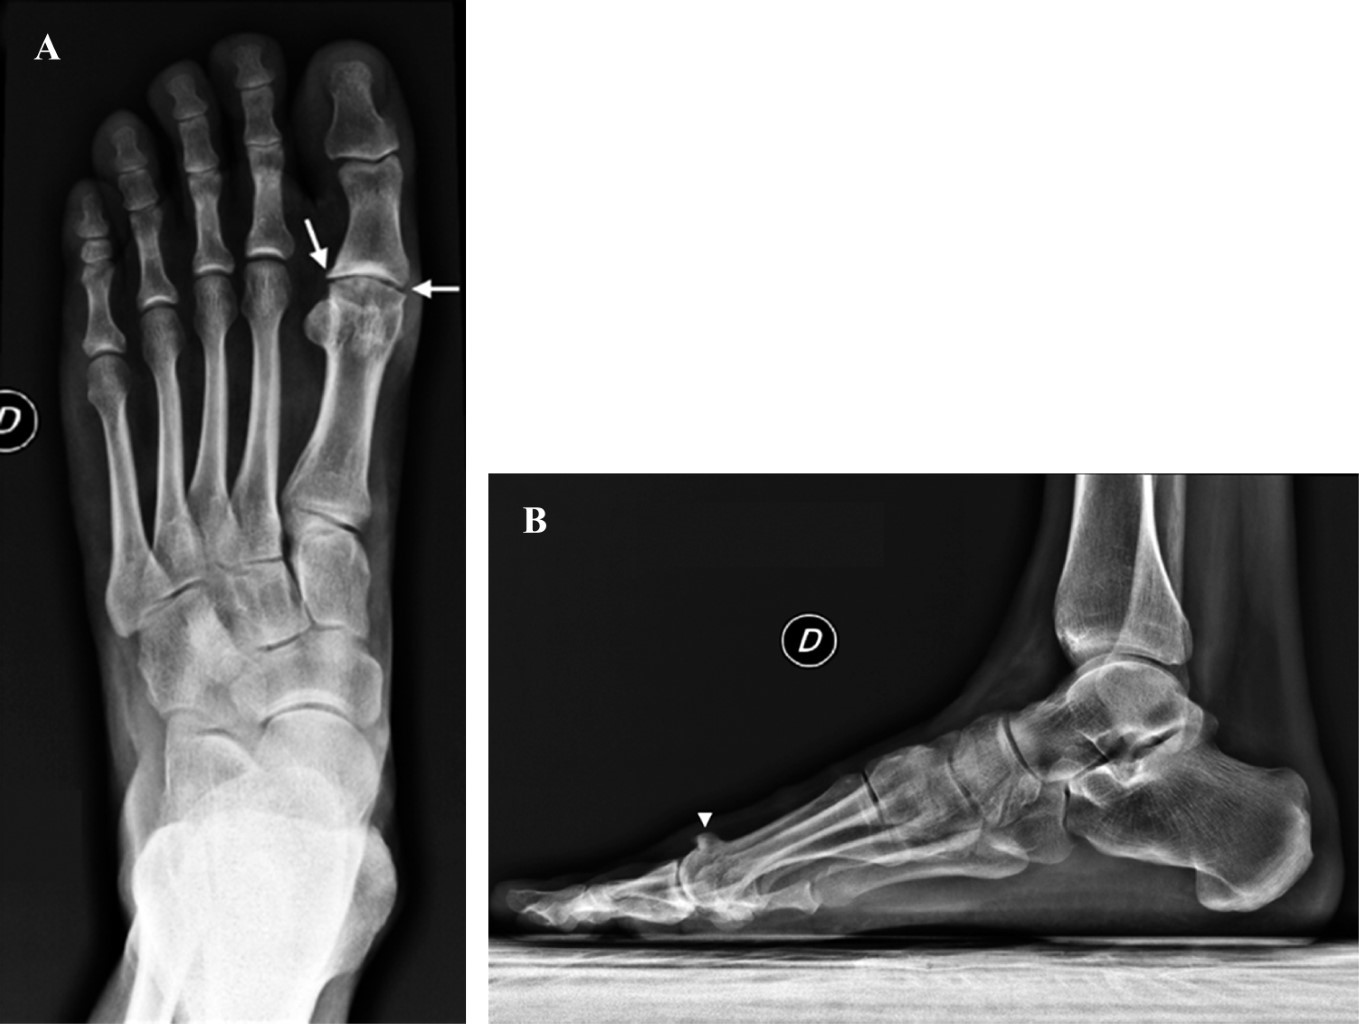

Se obtuvieron radiografías dorsoplantares y laterales con apoyo del pie derecho, que mostraron un espacio articular disminuido de la articulación metatarsofalángica del hallux predominantemente de la cara lateral, esclerosis subcondral y quistes con un osteofito dorsal en la cabeza del primer metatarsiano, así como presencia de pequeños osteofitos en la cabeza del primer metatarsiano y la base de la falange proximal del hallux (Figura 1).

Con base en los hallazgos radiográficos, se realizó el diagnóstico de hallux rigidus Coughlin y Shurnas etapa 3.

Figura 1